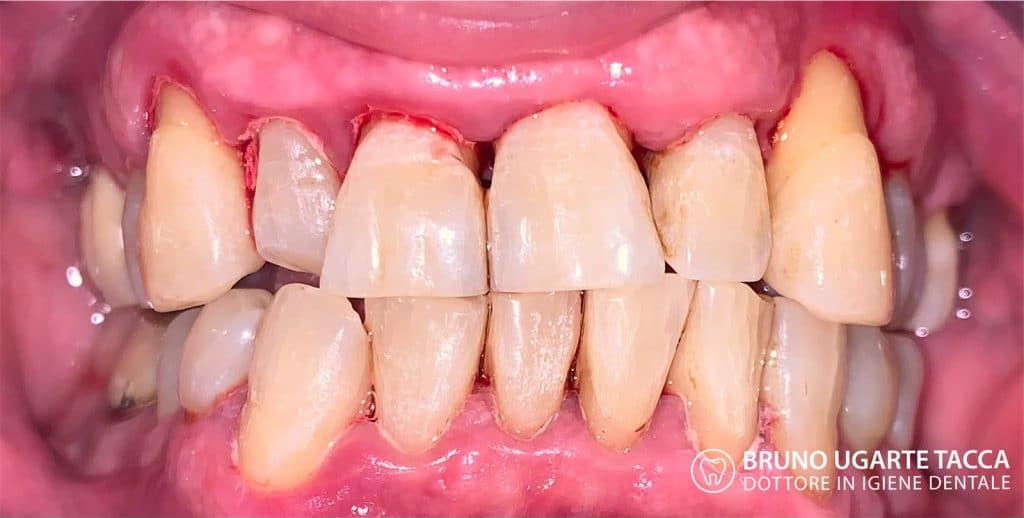

Performing the complete instrumentation

supragingival and subgingival with ultrasonic and / or manual instruments in one

single session or in two sessions at most performed over 2 days

consecutive. The original protocol also includes antiseptic therapy with

chlorhexidine performed in the chair immediately after the instrumentation as well